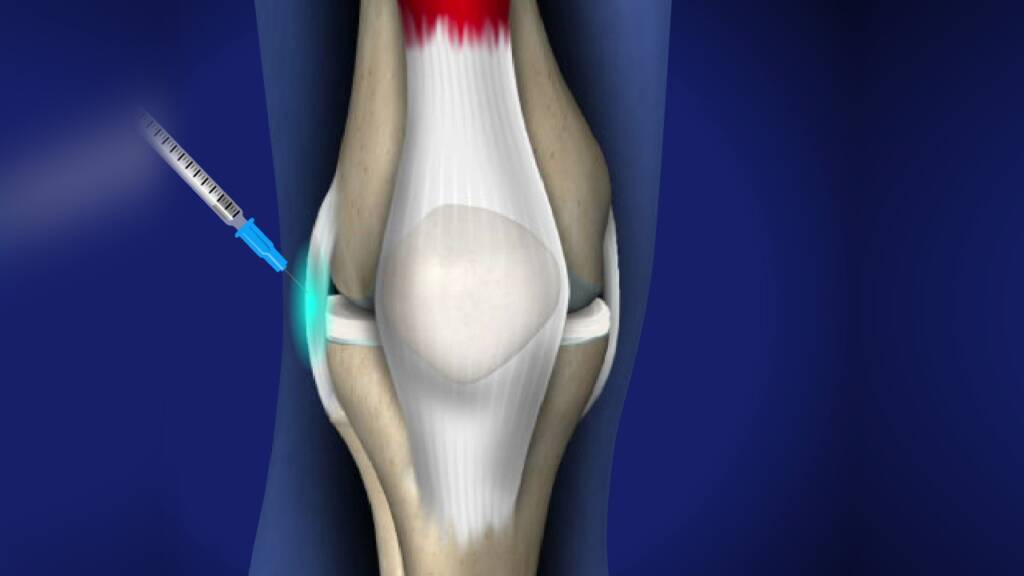

Interventional Pain Procedures